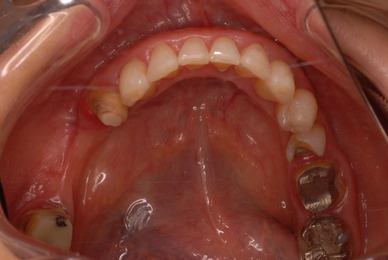

お口の中から差し歯、入れ歯、詰め物を追放しましょう!

口の中の病気を治し、病気を興さない医療を目指します。

二度とお口の中へ変なものを入れなくても済むように

予防に精進いたしましょう!安全な矯正、美容を目指しましょう!